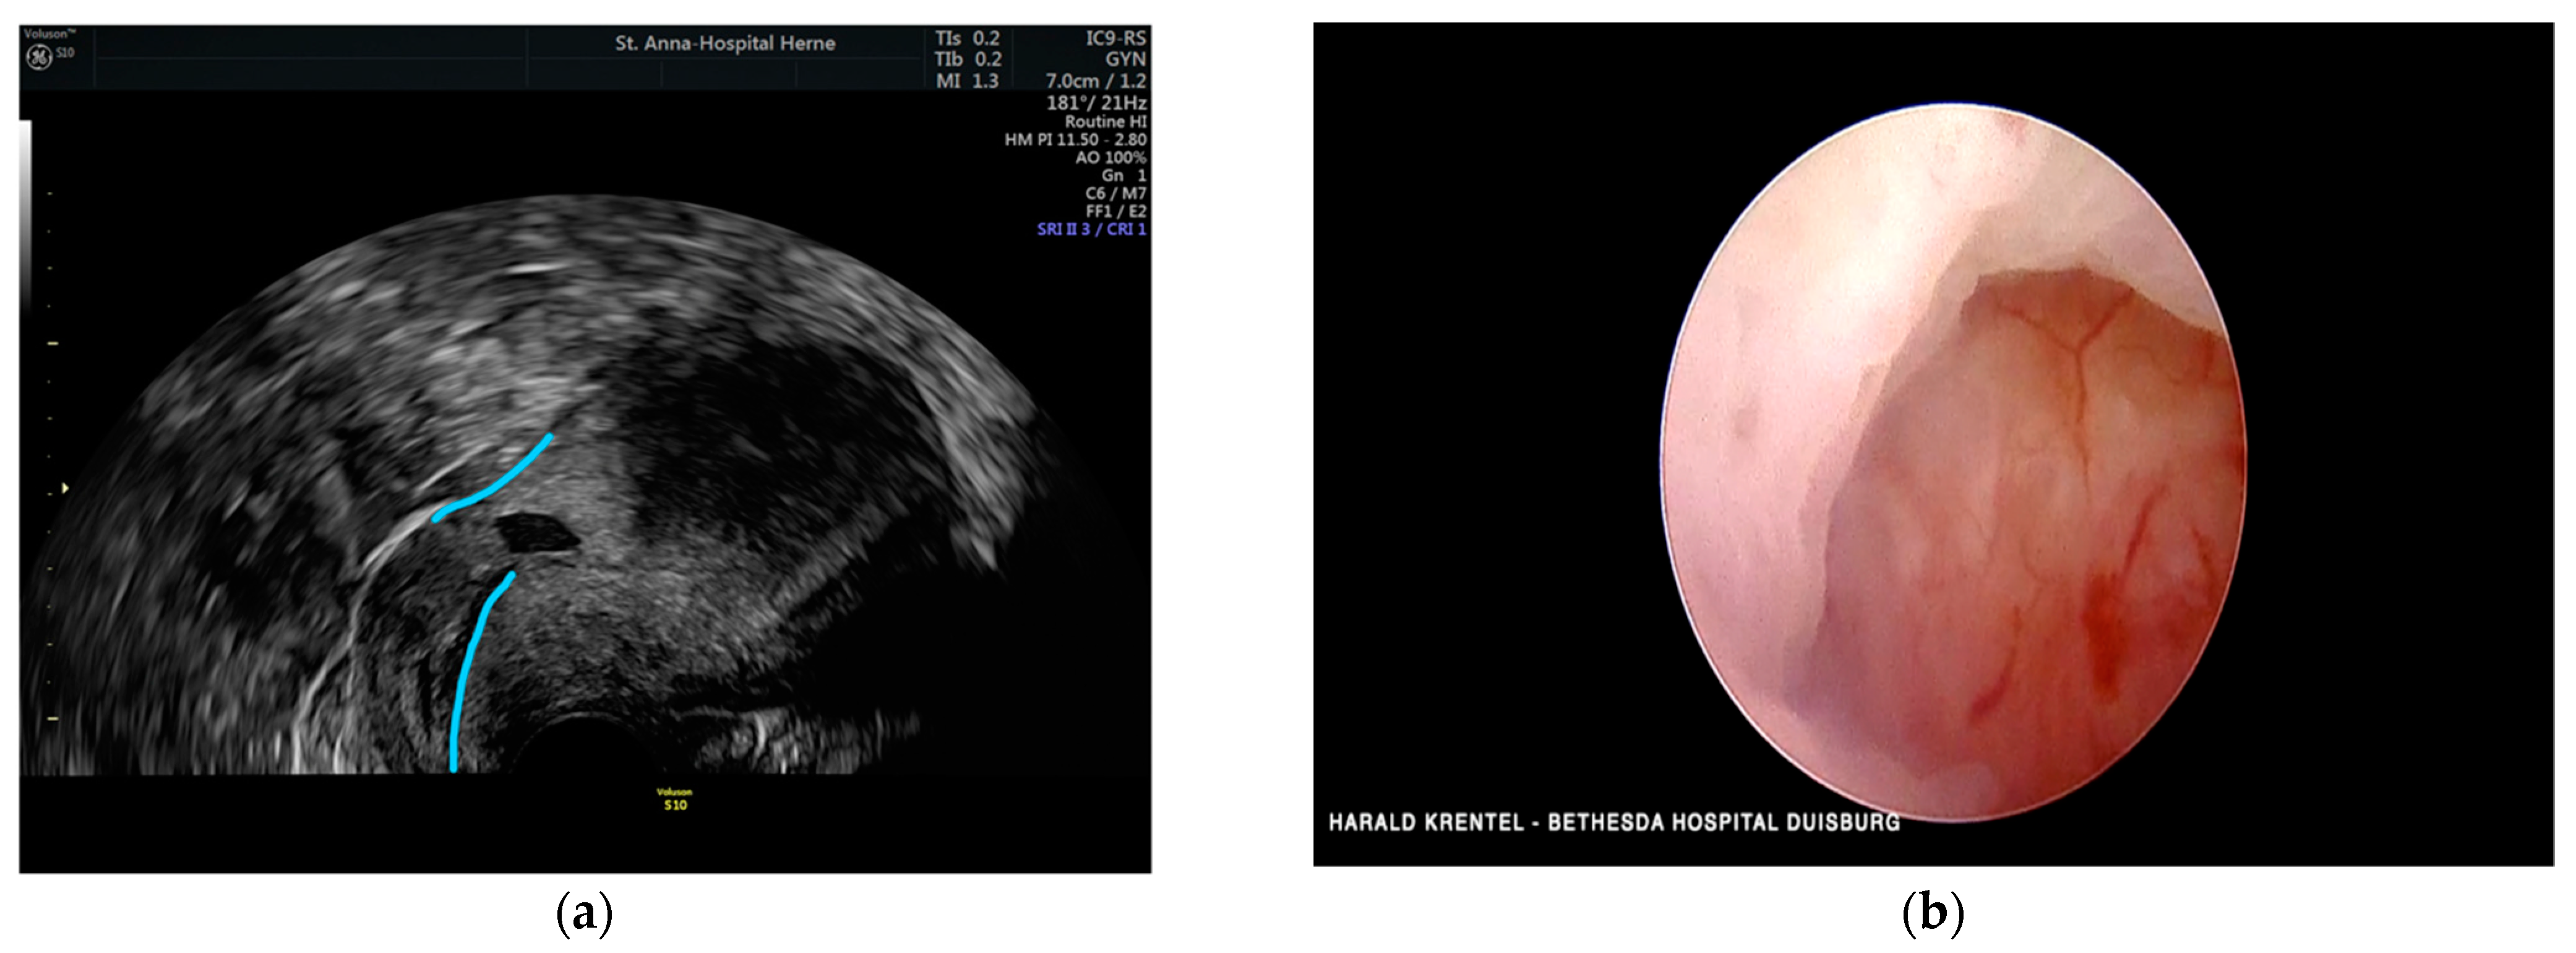

3.9. Case 9 —Symptomatic Isthmozele—Laparoscopic Treatment